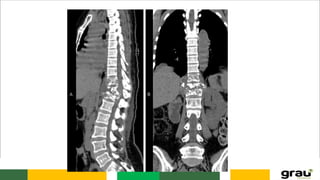

Coluna Vertebral

A coluna é formada de 33 vértebras:

• 24 pré-sacrais, sendo 7 cervicais, 12 torácicas e 5 lombares;

• pelo sacro composto de 5 vértebras fundidas e pelo cóccix formado de 4

vértebras rudimentares fundidas entre si, sendo que a 1a

. vértebra coccígea,

um pouco mais volumosa, se articula com o ápice do sacro através de um

disco intervertebral rudimentar.

A coluna cresce até os 25 anos e diminui na velhice, devido à redução na altura

dos discos e dos corpos vertebrais.

CURVATURAS: Primárias e secundarias

IMPORTÂNCIA CLINICA: hipercifose, hiperlordose escoliose